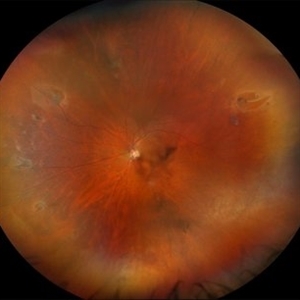

59 year-old patient presents with total retinal detachment at first visit in OD. Recommending prompt surgical intervention.

Photographer: Korey Starkey

Imaging device: Optos

Condition/keywords: color fundus photograph, Optos, retinal detachment, total retinal detachment